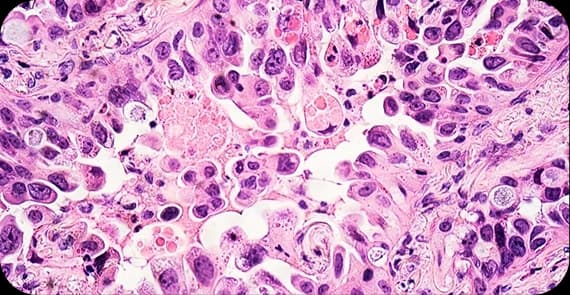

There are different types of colon cancer depending on the cell origin.

The most common type, arising from glandular cells lining the colon.

A subtype that produces mucus and may behave differently from typical adenocarcinoma.

A rare and more aggressive variant.